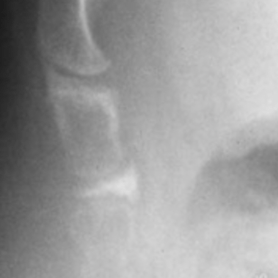

Ci-dessous : luxation n’apparaissant que sur le cliché en position assise

La luxation est la lésion coccygienne la plus frappante. Elle représente environ 20% des coccygodynies chroniques. En dehors de quelques rares cas de luxation permanente, elle ne survient qu’en position assise et se réduit spontanément lorsque le patient se lève. Ceci explique qu’elle n’ait pas été individualisée avant nos travaux. La luxation survient sur un coccyx plutôt droit, à faible rotation pelvienne et incidence élevée. Disques sacro-coccygiens et inter-coccygiens sont concernés à égalité. Le déplacement du coccyx se fait toujours vers l’arrière. L’analyse d’une série témoin a montré qu’il devait dépasser 20% (selon une mesure analogue à celle utilisée pour les spondylolisthésis) pour être significatif.11 En général, le recul est de 50 à 100% et il n’y a pratiquement jamais de discussion sur sa responsabilité dans la douleur. La luxation est la lésion post-traumatique par excellence. La faible rotation pelvienne et l’incidence élevée se traduisent par un coccyx ressorti vers l’arrière lors de la chute, donc particulièrement exposé aux blessures. Elle survient plus souvent en cas de surcharge pondérale, non que les obèses se fassent plus mal en tombant, mais en raison de leur façon spécifique de s’asseoir, comme le montre la faible rotation pelvienne sagittale (moyenne < 30°), ce qui signifie qu’ils ont tendance à se laisser tomber sur le siège. En cas de luxation, la douleur coccygienne présente deux caractéristiques qui permettent de la suspecter dès l’examen clinique : elle survient immédiatement, dès que le patient s’assoit et elle s’accompagne souvent d’une douleur au relever (qui est parfois le seul symptôme). Son intensité est plus marquée que pour les autres causes, ce qui pousse les patients à consulter plus rapidement.